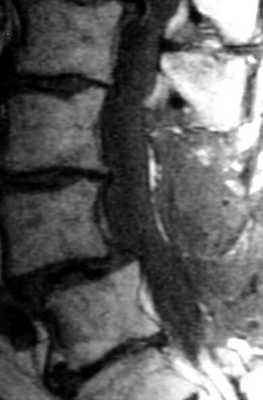

МРТ поясничного отдела позвоночника. Т2-взвешенная сагиттальная МРТ. Стеноз позвоночного канала.

МРТ поясничного отдела позвоночника. Рецидивная грыжа диска. Т2-зависимые МРТ в сагиттальной и аксиальной плоскостях.